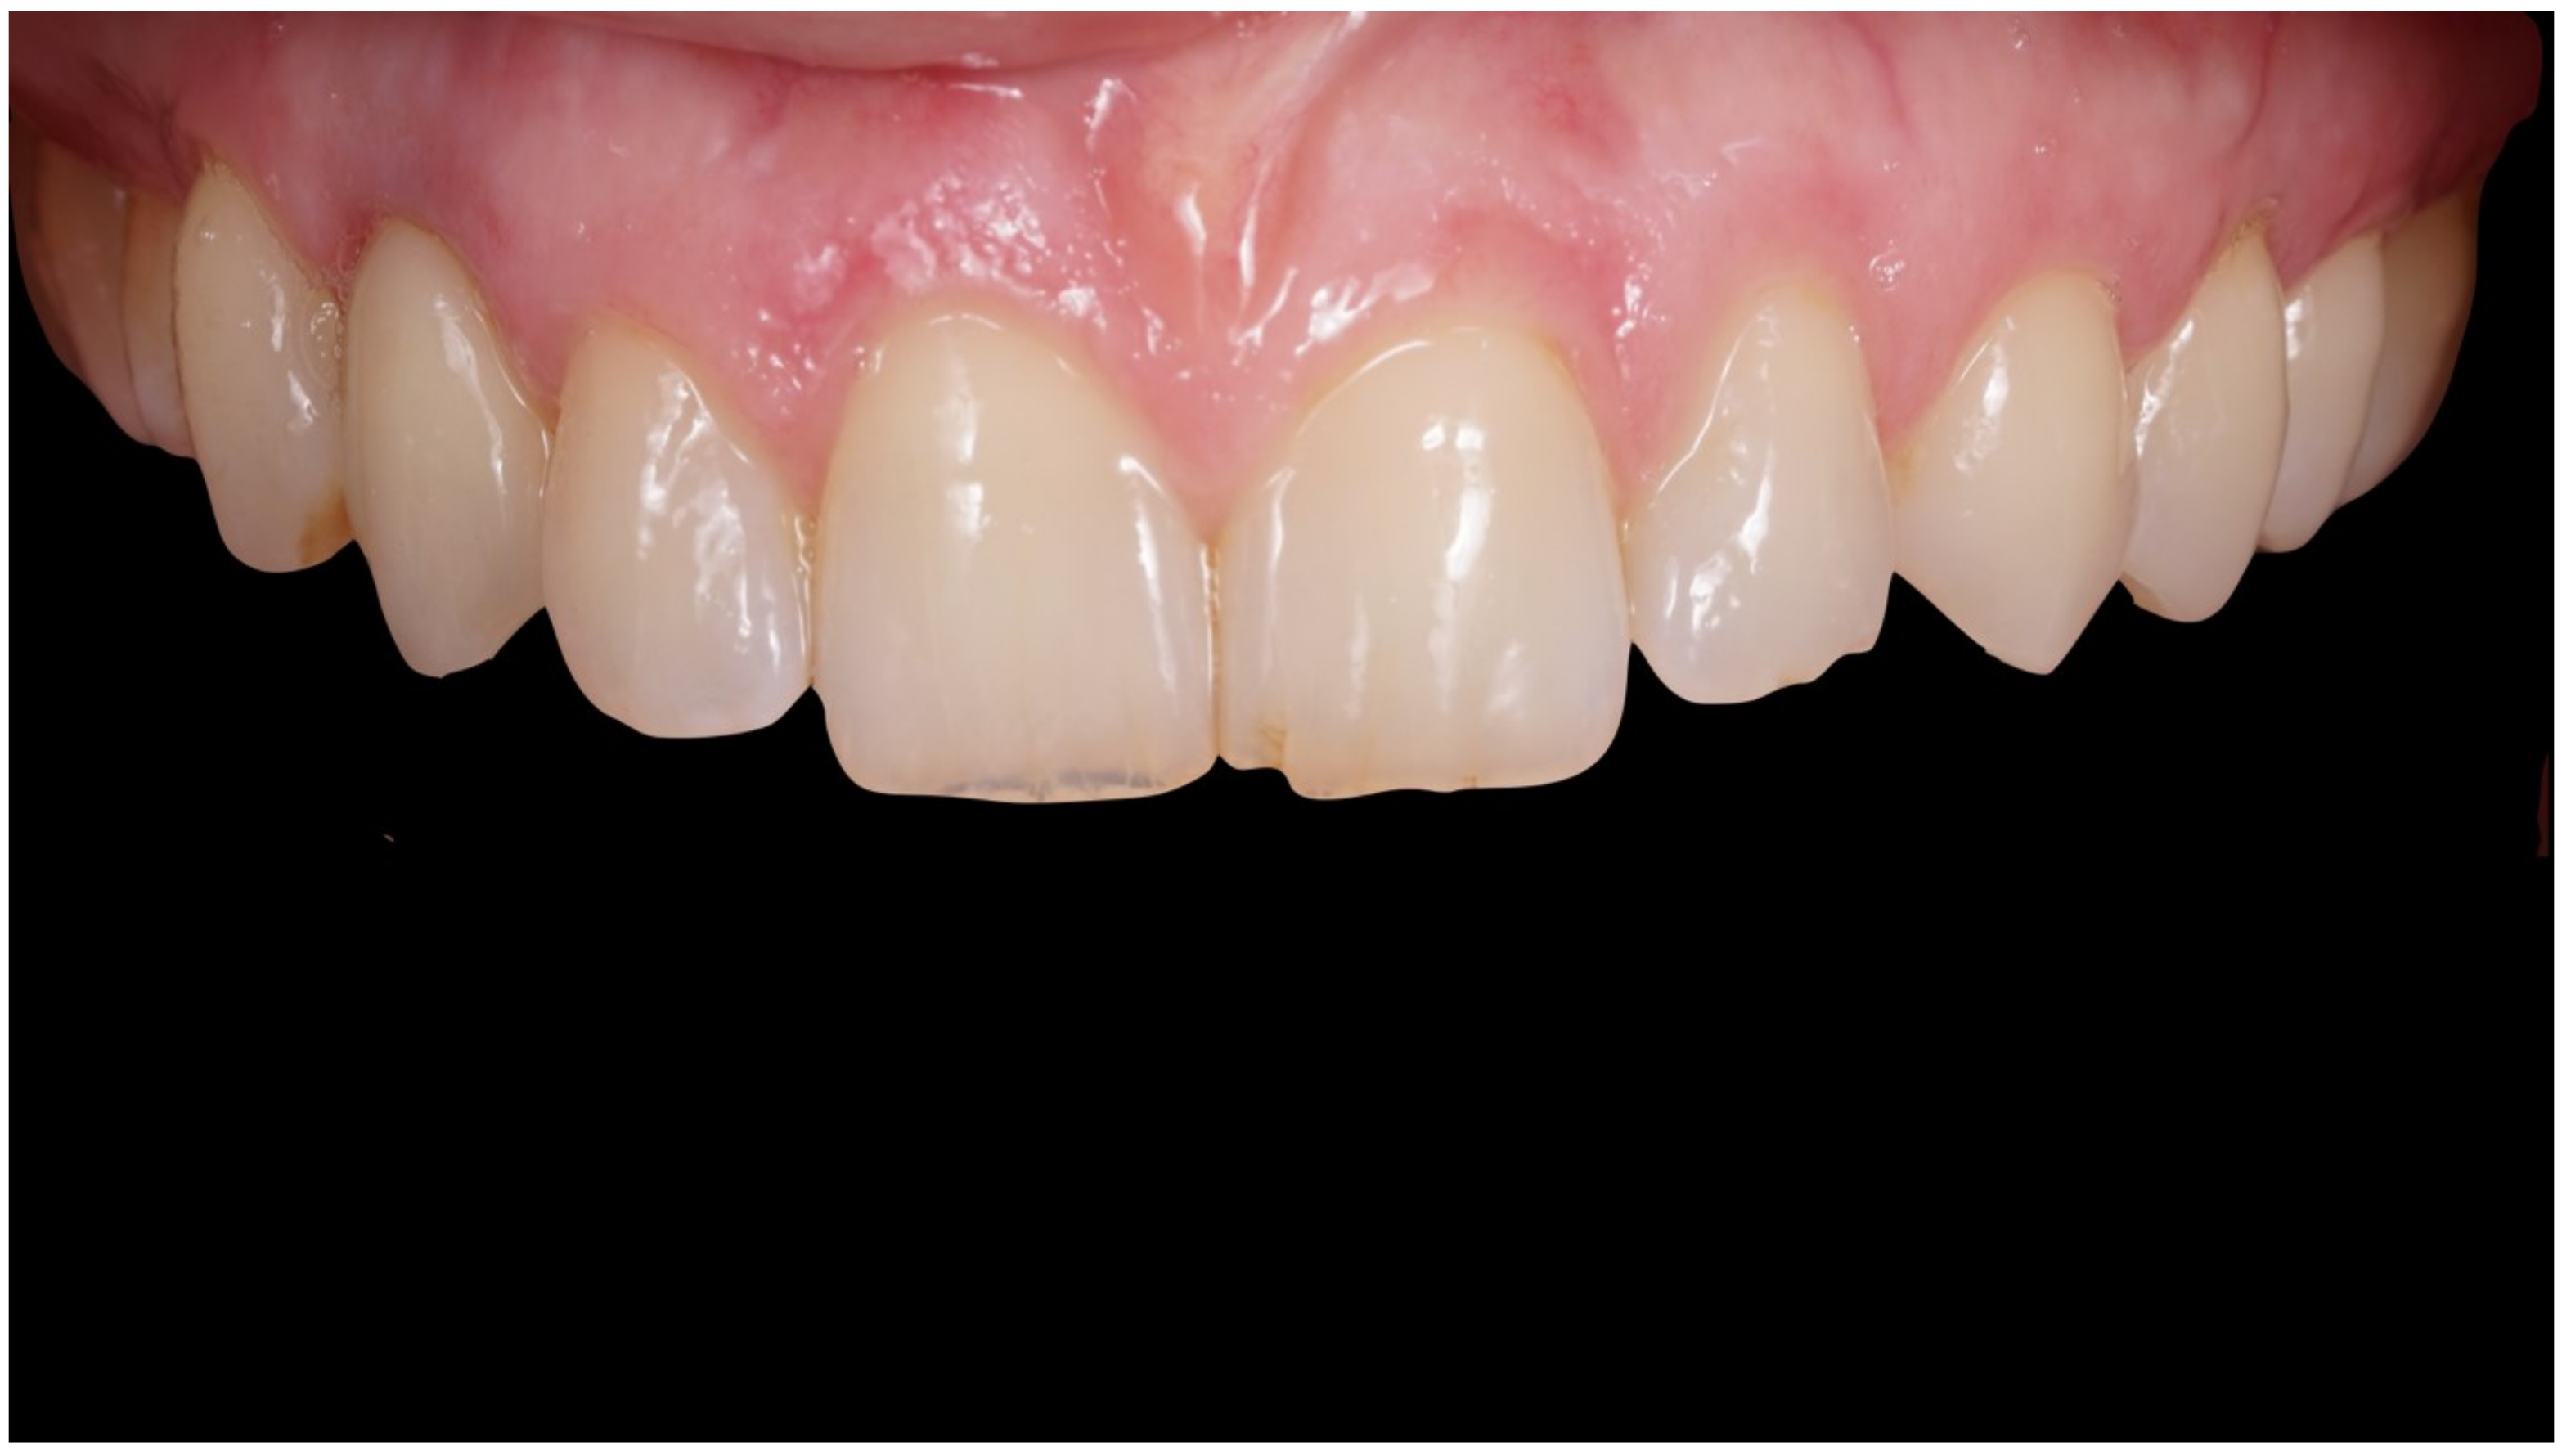

Figure 8.

Delivery of final crown.

Figure 9.

Definitive crown after 1 year of follow-up, frontal view.